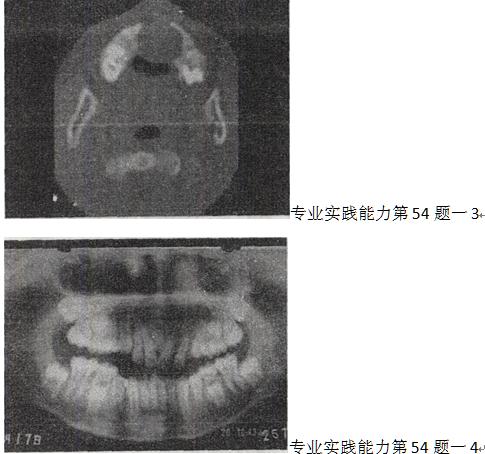

牙齿参差不齐,无发热,无疼痛,PE:上牙槽向前隆突,影像检查如图,最可能诊断为

- A.上颌骨结核

- B.上颌骨囊肿

- C.上颌骨脓肿

- D.上颌骨造釉细胞瘤

- E.上颌骨巨细胞瘤